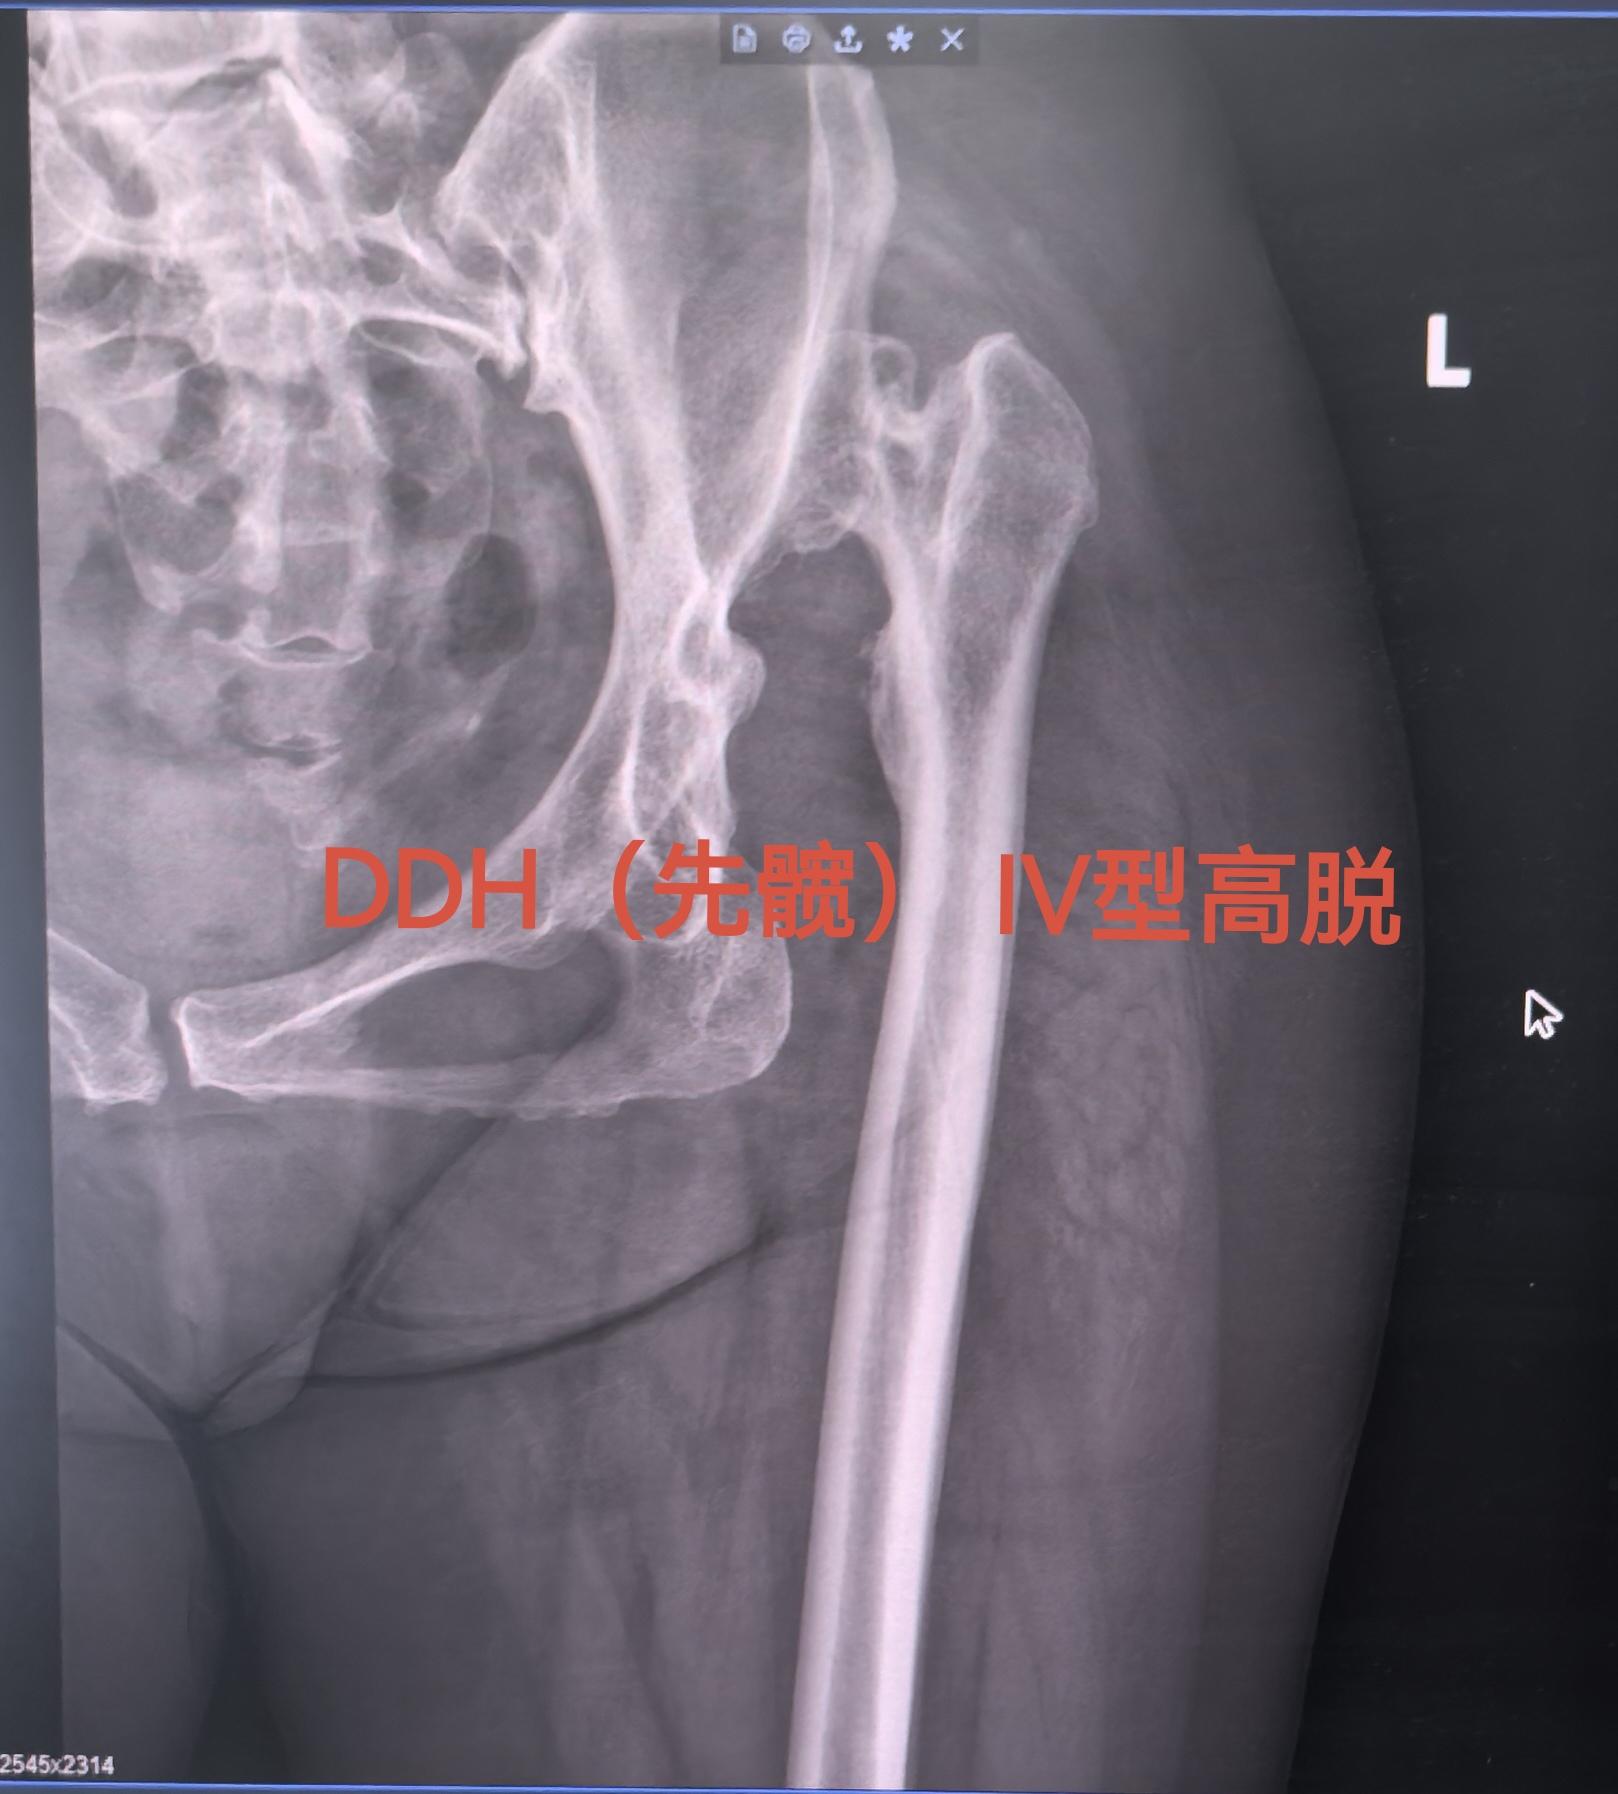

DDH先髋,高难度。DDH  Crowe IV型,高难度手术,半个骨盆...